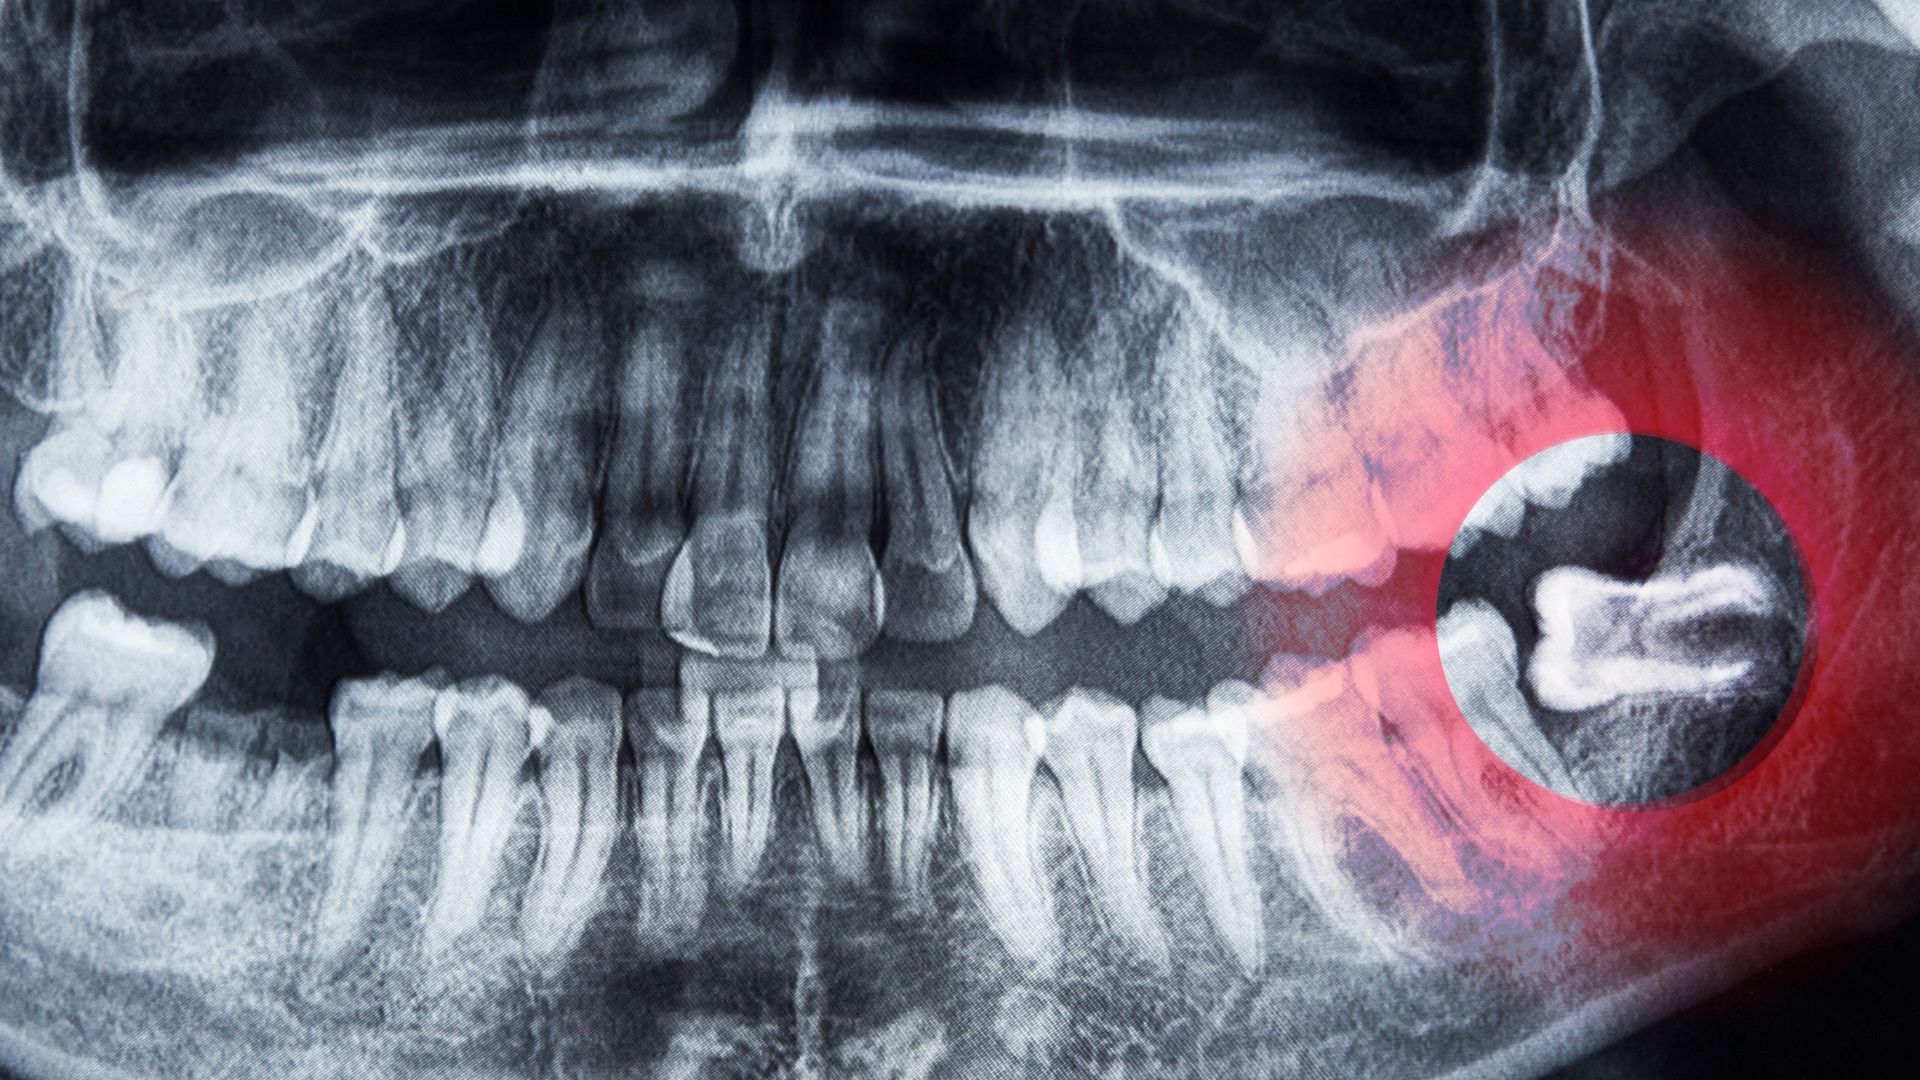

- Phim X-quang răng hoặc CT Cone Beam giúp bác sĩ xác định rõ vị trí răng, hướng mọc và các dây thần kinh xung quanh để lập kế hoạch can thiệp chính xác.

Theo các nghiên cứu nha khoa, khoảng 60 - 80% răng khôn ở người trưởng thành mọc bất thường (lệch hoặc ngầm) khiến việc nhổ phức tạp hơn so với các răng khác. Chính những yếu tố này làm nhiều người lo lắng về khả năng nguy hiểm khi nhổ răng khôn.

Cao | Răng mọc ngầm hoàn toàn, lệch nặng, sát dây thần kinh hoặc xoang. | Nguy cơ tổn thương thần kinh (tê tạm thời 1 - 5%), khô ổ răng cao hơn, nhiễm trùng, ảnh hưởng xoang. |